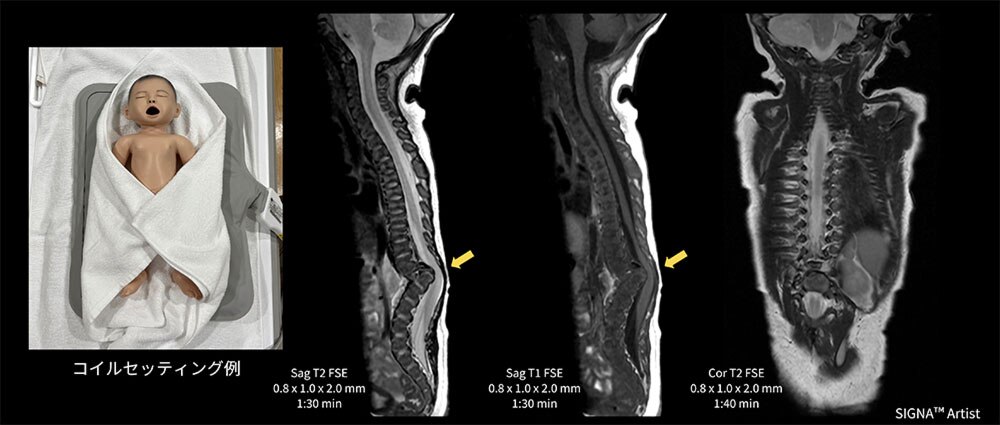

Case3 新生児の脊椎検査

生後7日の新生児。出生前MRI検査時に脊椎異常を指摘されており、出生後に脊椎MRI検査を実施。

Spineコイルや従来からあるGEM Flex Coilを検討したが、対象が小さい事やコイルの硬さ、また体動や固定が懸念された。MP Coil自体クッション性があるので、MP Coilの上に仰臥位のポジショニングで、固定も問題なく検査が施行できた(図5)。Th10~L1は分離不能で急峻な後湾変形を認め、脊柱管はこの上下で狭小化。脊髄空洞症や脂肪腫は認めず分節性脊椎形成異常症と診断された一例。

図5 新生児の脊椎検査におけるMP Coilのセッティング例と臨床画像